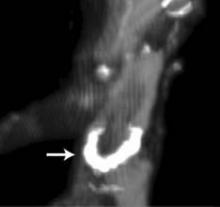

Abbott announced positive long-term results for the company's innovative Absorb Bioresorbable Vascular Scaffold (BVS). Three-year results from 101 patients in the second stage of the ABSORB trial were presented at the 62nd Annual Scientific Session of the American College of Cardiology (ACC) in San Francisco. Absorb is commercially available in Europe as well as other international markets and is an investigational device in the United States.